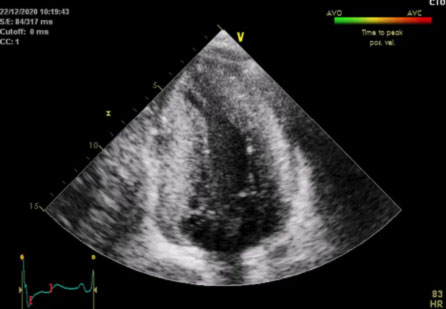

La sindrome di Noonan

“Trattiamo le aritmie cardiache dallo studio dei geni all’ablazione transcatetere“